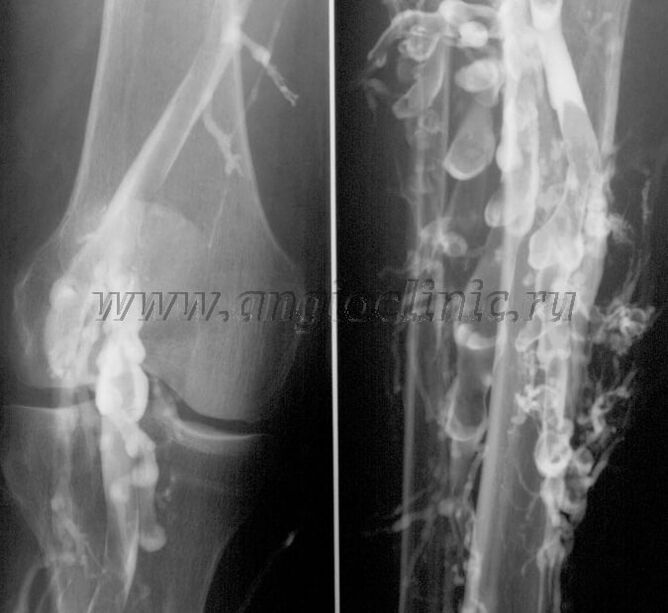

Contrast venography

Usually, ultrasound scanning is sufficient for a full diagnosis of venous pathology, but in some cases it is necessary to study the relationship between the state of the deep and superficial venous system, especially in case of relapses of varicose veins and secondary varicose veins.

To solve these problems, contrast X-ray examination is used.The saphenous veins are punctured and contrast is administered.The movement of the contrast is observed on the monitor of the X-ray machine, and all necessary tests and projections are carried out.Currently, venography for varicose veins is used very rarely.